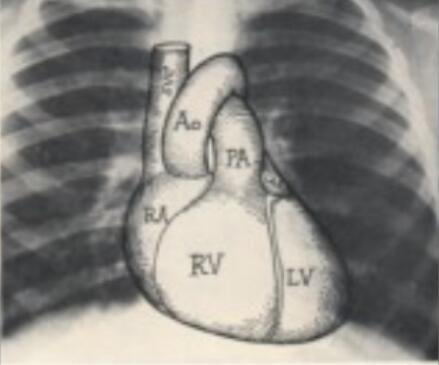

推进医养结合是完善养老服务机制,激活养老服务市场的重要内容和手段,也是基层医疗机构服务的重点之一。养老服务体系对影像技术人才的需求进一步加大。但招聘岗位以影像诊断和超声诊断为主,影像技术专业学生不能独立胜任岗位。所以临床医学专业影像诊断和超声诊断的就业岗位比较多,主要有:放射科(包括X线摄影、CT、MRI、DSA等)影像诊断人员、超声诊断操作人员、社区医院影像科工作人员(技术及诊断)和医学影像技术教学科研辅助人员。

临床医学专业影像诊断和超声诊断的就业岗位比较多,主要有:放射科(包括X线摄影、CT、MRI、DSA等)影像诊断人员、超声诊断操作人员、社区医院影像科工作人员(技术及诊断)和医学影像技术教学科研辅助人员。

答:影像诊断培养的是放射医师,超声诊断培养的是超声医师,有诊断权,就业方向不同。

答:影像诊断:一年级第二学期——影像检查技术学

答:影像专业课程与临床紧密相关,在解剖学的基础上结合生理、病理、诊断、内、外、妇、儿等课程,根据影像图像做出诊断,协助临床医生确诊疾病。所以临床课程是基础,层层递进。